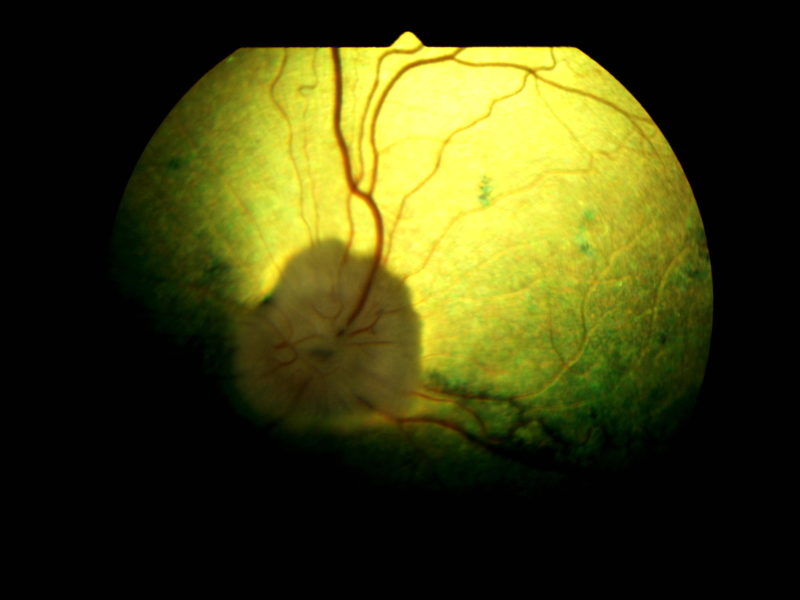

Bei der klassischen PRA beginnen die „Stäbchen“ die für das Nachtsehen zuständig zuerst zu degenerieren bzw. abzusterben. Dieser Vorgang ist nicht schmerzhaft. Im Anfangsstadium ist auffällig, dass sich die Tiere im Dämmerlicht oder im Dunkeln unsicher bewegen, ängstlich sind und unbekannte Objekte oder Personen verbellen. Teilweise stoßen die Tiere auch gegen ihnen unbekannte Dinge an oder weichen dem Besitzer nicht mehr von der Seite. Ein weiteres Zeichen ist der unvollständige Schluss der Pupillen bei einfallendem Licht und ein stärkeres “Leuchten” der Augen in der Dunkelheit als gewöhnlich, was ein Zeichen für eine dünner werdende Netzhaut ist. Dadurch kommt die unter der Netzhaut gelegene Schicht, das leuchtende Tapetum lucidum, verstärkt zum Vorschein. Diese Symptome verschlechtern sich dann in den darauffolgenden Monaten bis Jahren und führen zu einer spürbaren Sehverschlechterung auch im hellen Licht, da dann auch die „Zapfen“ beginnen zu degenerieren. Auch dieser Vorgang ist nicht schmerzhaft. Zwischen den ersten Symptomen und der vollständigen Erblindung vergehen in der Regel 3-6 Jahre.  Selten gibt es PRA Formen, bei welchen zuerst die Zapfen und im Anschluss daran die Stäbchen degenerieren. Dann tritt genau der umgekehrte Fall ein und die Tiere erblinden zuerst bei hellem Licht und anschließend auch bei Dunkelheit, dies sind Sonderformen und enden leider auch immer mit der vollständigen Erblindung des Tieres. Eine häufige Folgeerkrankung der PRA stellt der graue Star (Katarakt oder Eintrübung der Linse) dar. Als Folge des grauen Stars kann nach einigen Jahren der grüne Star (Erhöhung des Augeninnendrucks) auftreten. Der grüne Star gehört mit zu den schmerzhaftesten Erkrankungen des Auges und kann zum Verlust des gesamten Augapfels führen. Aus diesem Grunde sollten Tiere, die an der PRA erkranken, ca. einmal jährlich zu einer Kontrolluntersuchung der Augen vorgestellt werden, damit weitere Folgeschäden frühzeitig erkannt und dann behandelt werden können, um schmerzhafte Zustände zu vermeiden.

Ein auf Augenerkrankungen spezialisierter Tierarzt (Veterinär-Ophthalmologe) kann die Diagnose PRA anhand der typischen Symptome und der Befunde stellen, sobald die Erkrankung klinisch ausgebrochen ist, d.h. sobald auch nur geringe Anzeichen einer Sehschwäche auffällig werden. In Einzelfällen, in denen z.B. der graue Star die Sicht auf die Netzhaut verhindert, kann die Diagnose auch mit Hilfe eines Elektroretinogrammes (ERG) gestellt werden. Das ERG ist eine Untersuchung der Netzhautfunktionen, die mit einem EKG (Elektrokardiogramm) des Herzens verglichen werden kann.